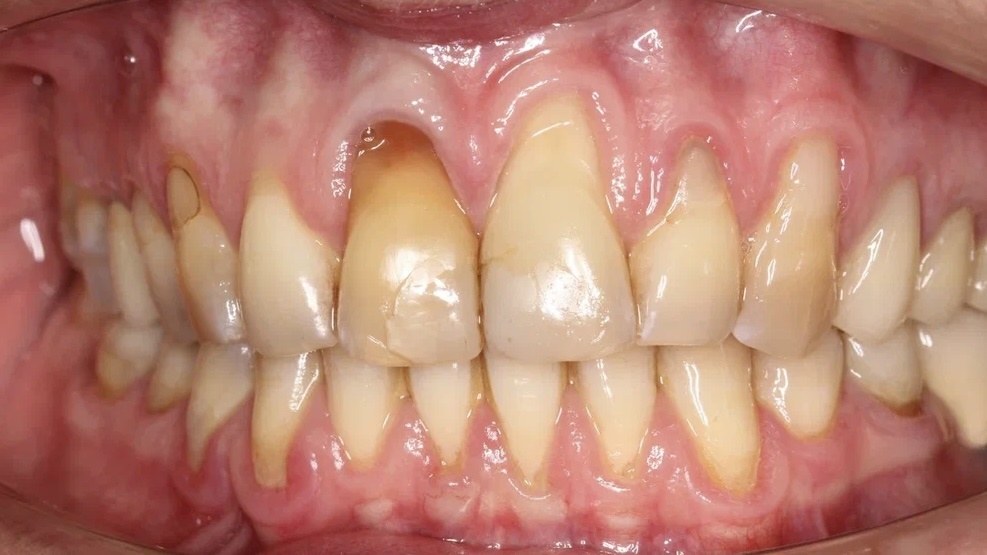

Восстанавливаем эстетику улыбки с рецессией десны

Пациентка обратилась к нам в клинику с жалобой на внешний вид зубов. Диагностика клинической ситуации показала наличие кариесов, рецессии десны, а также нездоровый цвет эмали. План лечения, составленный командой специалистов клиники «Два Дантиста», включал в себя ряд стоматологических процедур, направленных на оздоровление всей полости рта, подготовку к протезированию и исправлению эстетики. Клинические случаи с комплексным лечением является рекомендованным восстановлением для всех пациентов. В данной ситуации, например, игнорирование лечения кариеса могло привести к развитию осложнений, потере зуба, распространению инфекции. Рецессия десны — это появление таких последствий, как повышенная чувствительность зубов, увеличение риска кариеса корня зуба, воспаления и пародонтит, потеря зуба и эстетические проблемы. Нарушение эстетики внешнего вида улыбки приводит к неуверенности в себе, что способствует возникновению психологических, социальных и профессиональных проблем. Заботьтесь о зд

Пациентка обратилась к нам в клинику с жалобой на внешний вид зубов. Диагностика клинической ситуации показала наличие кариесов, рецессии десны, а также нездоровый цвет эмали.

План лечения, составленный командой специалистов клиники «Два Дантиста», включал в себя ряд стоматологических процедур, направленных на оздоровление всей полости рта, подготовку к протезированию и исправлению эстетики.